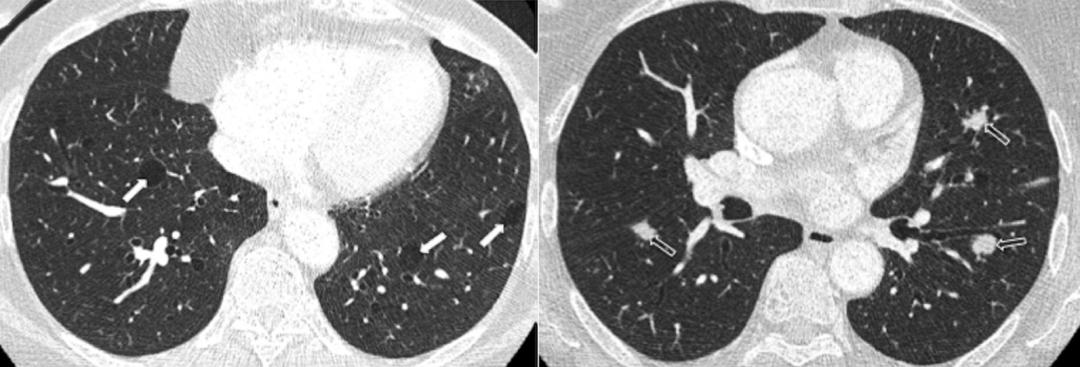

肺朗格汉斯细胞组织细胞增多症(PLCH)要注意囊和结节的特征,它囊性病变的囊壁相对较厚,还可能看到一些结节,所以我们如果看到不规则的、囊壁稍厚、有结节的、分布在中上肺的就一定要注意鉴别PLCH。下面两张影像分别提示我们要注意囊和结节、注意区域分布。

图:PLCH患者的影像,注意囊和结节

图:PLCH患者的影像,注意区域分布